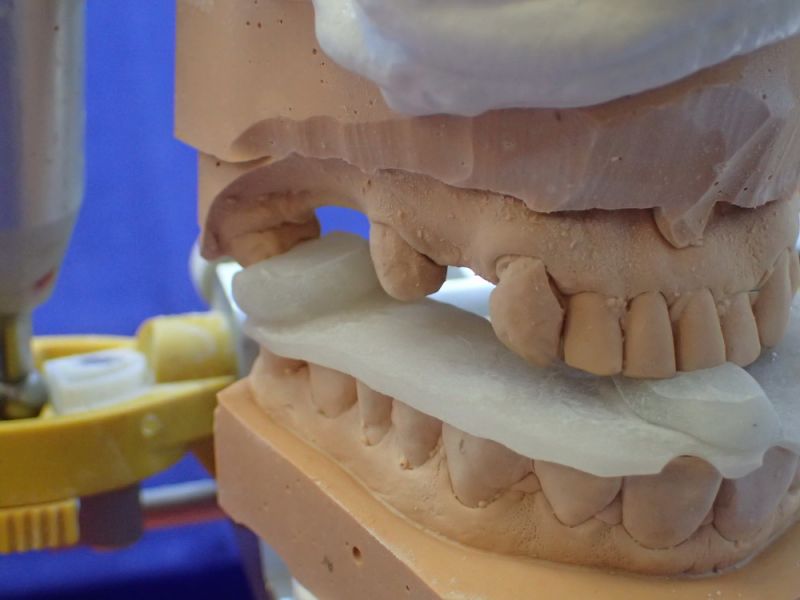

2. Herstellung und Eingliederung eines adjustierten Aufbissbshelfs

Erkennbar ist die massive Abweichung der habituellen Bisslage von der neuromuskulär zentrierten Bisslage.